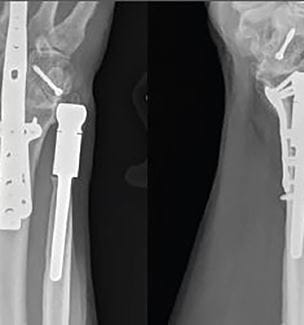

Case Study: Constrained Arthroplasty of Distal Radioulnar Joint After Severe Fracture

Innovations in Orthopaedics - Winter 2017 Download PDF In 2012, a 57-year-old man working at a job site fell from an elevated height and landed on his right arm. His arm buckled, cleanly breaking the ends of his radius and ulna at the wrist...